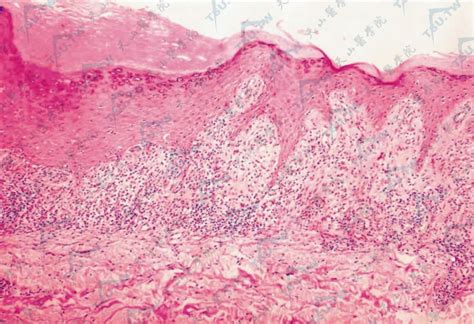

扁平苔藓图片